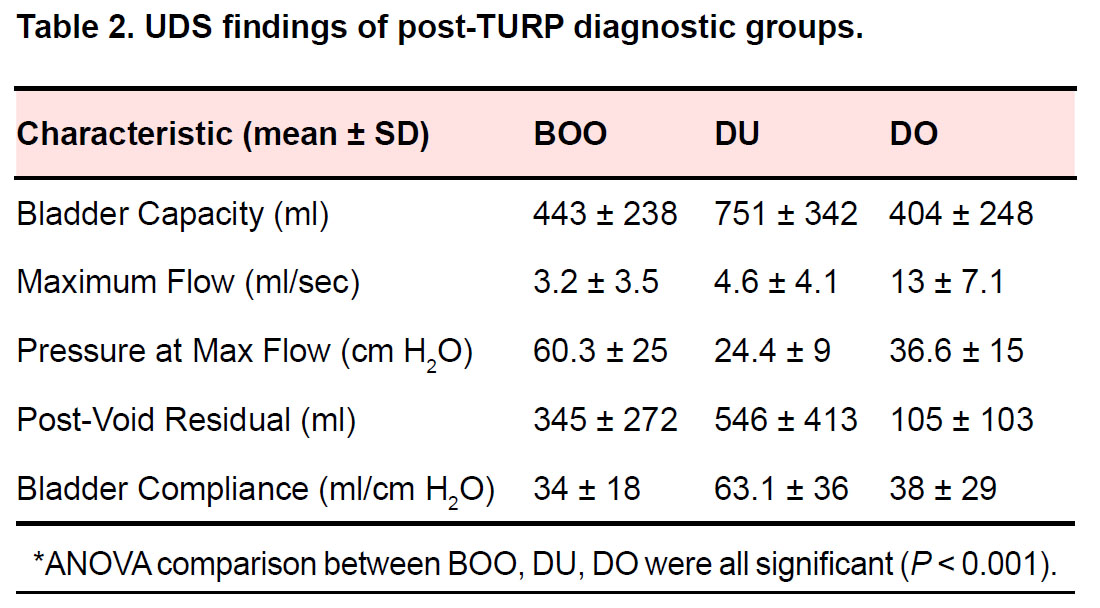

Characterization of men with lower urinary tract dysfunction after surgical management of benign prostatic obstruction

Abstract 148 | HTML Downloads 51 PDF Downloads 59 | DOI https://doi.org/10.14440/bladder.2014.28Page e6